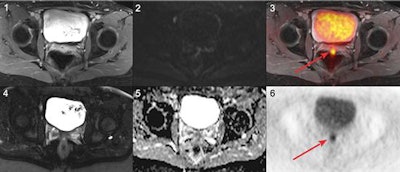

Based on the reference standard, 55 patients (77%) experienced a cancer recurrence, while 16 patients (23%) had no such recurrence. PET/MRI correctly identified all 55 patients (100%) with cancer recurrence compared with MRI alone, which correctly identified 46 patients (83%) with cancer recurrence (p < 0.01). In addition, PET/MRI and MRI alone both correctly identified 15 (94%) of the 16 patients with no cancer recurrence.

While PET/MRI correctly identified all malignant lesions, the hybrid modality misclassified two foci of infection as malignant lesions. By comparison, MRI's missed 34 malignant lesions, which included 32 FDG-positive nonenlarged lymph node metastases. MRI alone also misinterpreted 12 malignant lesions as benign, which included four local recurrences and three peritoneal metastases.

Among the patients with recurrence in the pelvic cavity, PET/MRI identified all 15 patients (100%) compared with MRI alone, which correctly identified only 11 patients (73%) in this category. Among patients with distant metastases, PET/MRI correctly identified all 40 patients (100%), compared with 32 correctly identified patients (80%) by MRI alone.